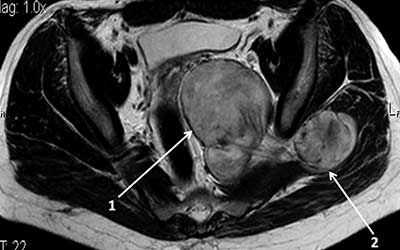

МРТ мягких тканей шеи. Т2-зависимая МРТ в аксиальной плоскости. Невринома.

Невриномы также располагаются между крупными сосудами, отодвигая их. Опухоль округлая, с четким контуром, хорошо контрастируется и в отличие от параганглиомы не содержит сосудистых включений.